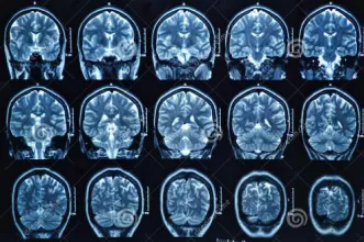

MRI也就是磁共振成像,屬于斷層成像的一種,它是利用磁共振現(xiàn)象從人體中獲得電磁信號,并重建出人體信息。通過檢查可獲得橫斷面、矢狀面、冠狀面的影像,空間分辨率高,是神經系統(tǒng)、脊柱脊椎部分檢測的第一選擇。

無論是DR還是CT,由于對部分軟組織的分辨率不足,所以軟組織疾病的排查便成了它們的短板,而磁共振的長處恰恰就是清晰顯示軟組織疾病,對于膀胱、直腸、子宮及關節(jié)肌肉的檢查優(yōu)于CT。MRI適用于神經系統(tǒng)病變、心血管系統(tǒng)、胸部病變、全身軟組織病變等。